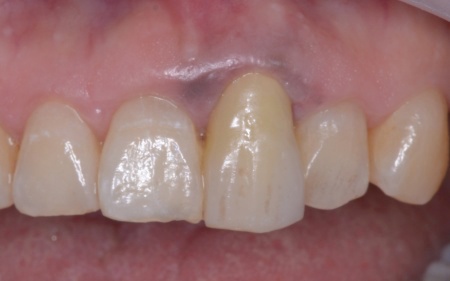

さらに患者様は全体的に歯並びや噛み合わせに問題があり、特に上下の前歯は噛んだ際に隙間ができ食べ物を噛み切りにくい状態です。

過去に矯正治療を受けていても、治療が不十分であったり治療後に歯並びが後戻りしたりすることで歯並びが乱れる場合があります。

さらに全体の噛み合わせを改善するため矯正治療を並行して行うこと、右上下奥歯の合わなくなった被せ物には矯正終了後に新しく作り直すこととしました。

②①と並行して上下歯列にワイヤー矯正のマルチブラケット装置を装着し、歯並びと噛み合わせを整える。

④矯正終了後に右上下奥歯の合わなくなった被せ物を除去し、自然な白さで強度もあるジルコニアセラミッククラウンを装着する。

最後に装着したジルコニアセラミッククラウンが歯に合っているか、噛み合わせに問題がないかを確認し、治療を終了しました。